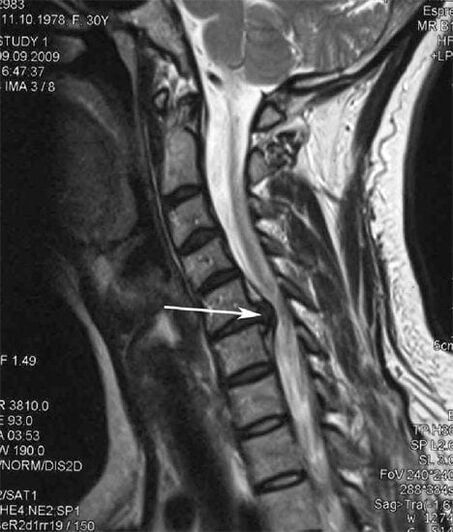

In the early stages, cartilage degeneration is detected by MRI.The pathology can then be diagnosed using x-rays.On radiography of the cervical spine, the distance between the vertebrae decreases, pathological changes in the facet joints and osteoporosis become noticeable.

Many people complain that they cannot turn their neck due to the severe pain that appears after suddenly lifting a heavy object.This phenomenon indicates the formation of a herniated disc.The cause of back, neck and upper limb pain is due to compression of one of the nerve roots protruding from the spinal cord.

| Cervical bone degeneration | The appearance of pathological changes in one or more motion segments of the spine.Impaired spinal mobility, development of myofascial pain syndrome and spinal root compression | Pain, paresthesia and movement disorders in the neck area, spreading to the back of the head and upper limbs.Detect characteristic changes in the spine on MRI and X-ray (osteoporosis, reduced distance between vertebrae, signs of damage to the intervertebral joints) |